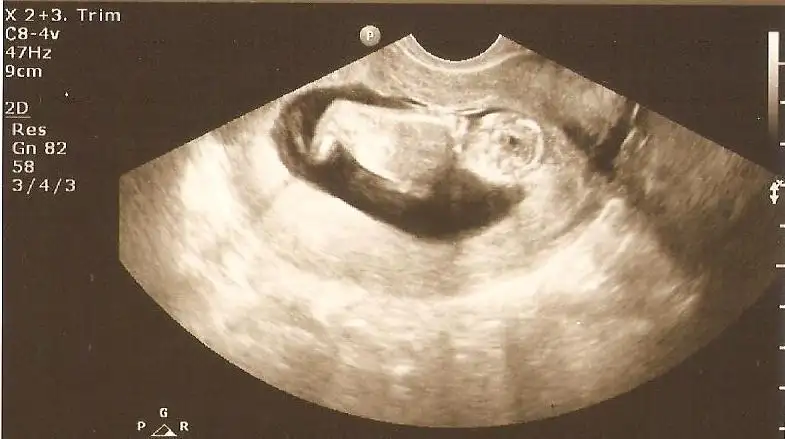

13+3 doktorun fikrini bugün söyledi ama sizde görün istedim bi bakar misiniz

Eklentiler